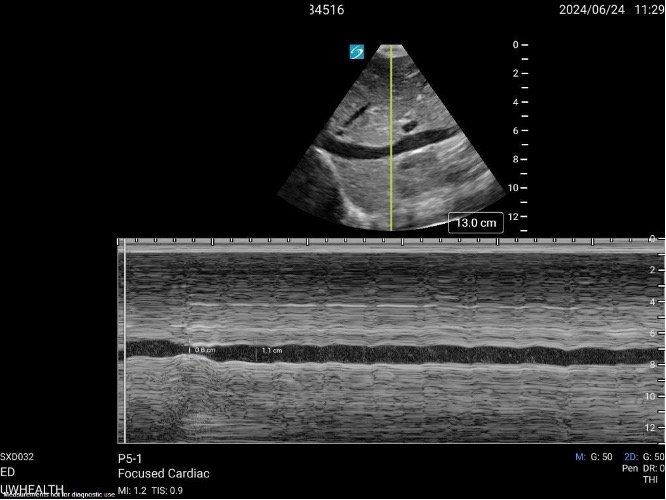

- Echocardiogram: A focused cardiac examination can help provide information on ventricular function, presence of pericardial effusion, and evidence of right heart strain.

- Inferior Vena Cava Evaluation: The ratio of the IVC (the caval index) to the aorta or the respiratory variation/collapsibility of the IVC can be correlated with hydration status. Variation in IVC diameter during respiration of >50% combined with an easily collapsible vessel suggests a low-volume state. In contrast, a variation of <50% with a distended or minimally collapsible IVC suggests a high-volume state or potential tamponade/obstructive physiology. In pediatrics, the IVC/aorta ratio can also be utilized. A ratio of less than one is seen in a low-volume state.

Figure: Subcostal view of the IVC in M-mode. Picture courtesy of Samuel Dillman, MD.